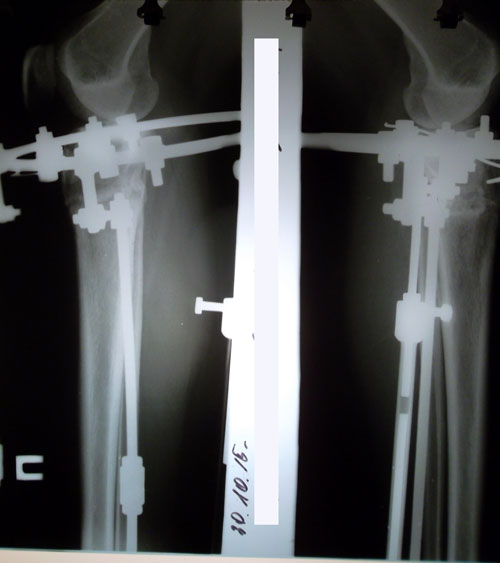

рентген в 60 дней.

У пациентке отличное сращение, можно хоть сейчас снимать аппараты bravo